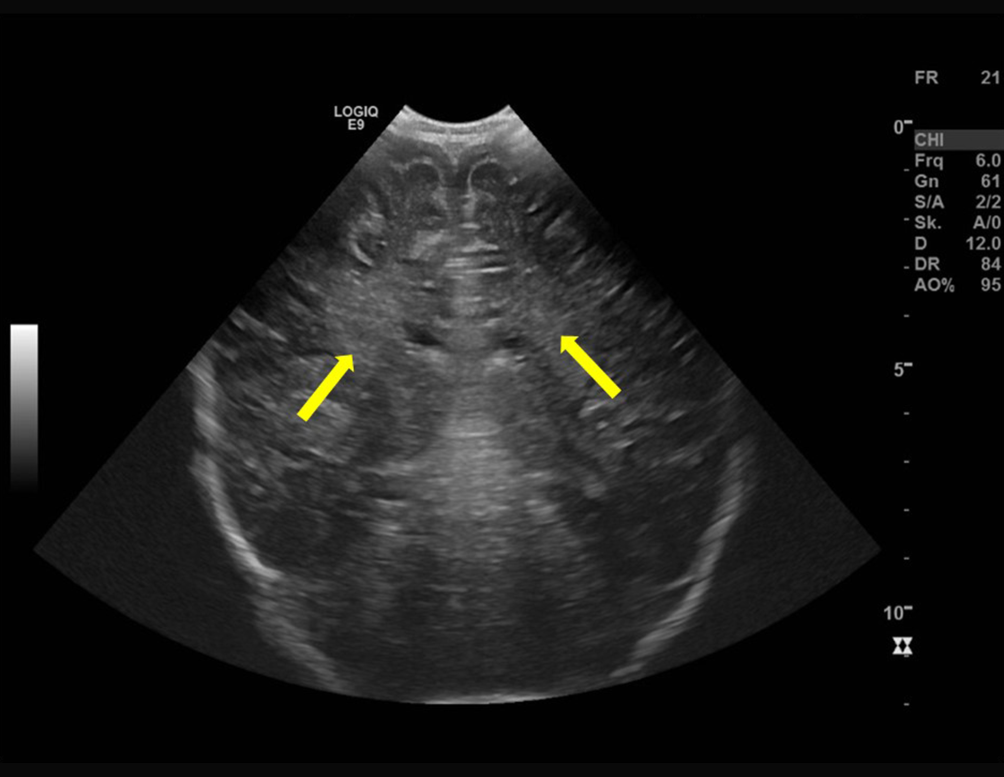

Abb. 1 (korrigierte Fassung)

Kraniale Sonographie, koronarer Schnitt, bei dem Patienten im Alter von sechs Monaten: angedeutete bilaterale periventrikuläre Echogenitätssteigerung (Pfeile)

Bild vergrößern